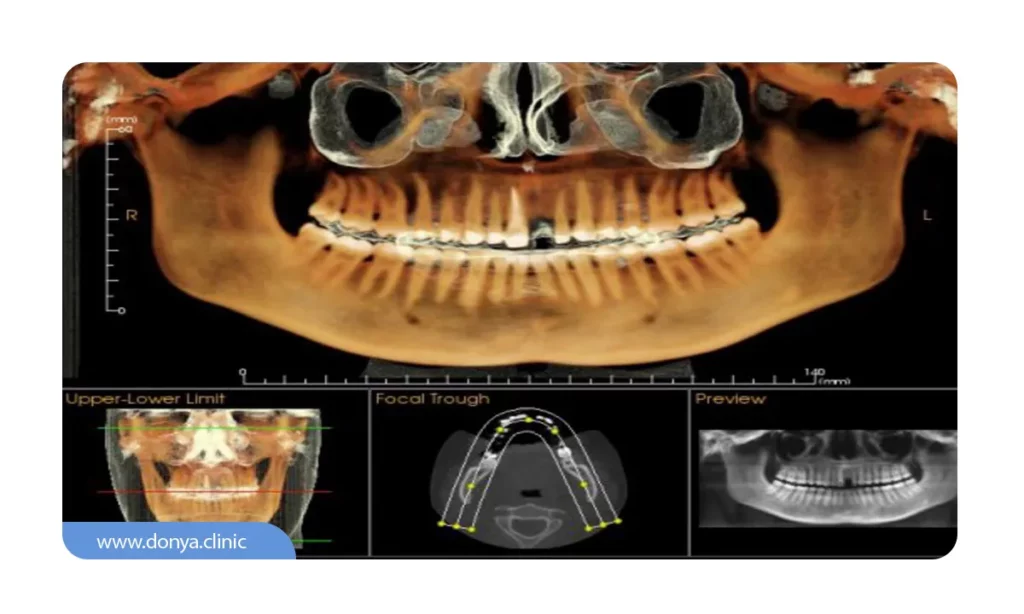

1️⃣ عکس CBCT (توموگرافی 3 بعدی)

عکس CBCT یا توموگرافی کامپیوتری با پرتو مخروطی، یک روش تصویربرداری سه بعدی است که از اشعه ایکس برای تولید تصاویر با کیفیت بالا از دندان ها و بافت های اطراف استفاده می کند. این تکنولوژی امکان مشاهده دقیق تری از بافت نرم و استخوان ها را فراهم می آورد و برای بررسی های دقیق تر و برنامه ریزی ایمپلنت های دندانی بسیار مفید است.

در مقابل، عکس OPG یا ارتوپانتوموگرام، یک تصویر دوبعدی پانورامیک است که تصویر کاملی از تمام دندان ها در فک های بالا و پایین را ارائه می دهد. این روش بیشتر برای تشخیص مشکلات کلی دهان و دندان مانند نامرتبی دندان ها، بیماری های لثه و شناسایی دندان های پوسیده استفاده می شود.

تفاوت اصلی بین این دو روش در نوع تصاویر تولیدی است؛ CBCT تصاویر سه بعدی ارائه می دهد که جزئیات بیشتری را نسبت به OPG نشان می دهد و برای بررسی های پیچیده تر مناسب است، در حالی که OPG برای بررسی های کلی و سریع تر مناسب است.

💵 هزینه عکس cbct در سال 1404 برای هر نیم فک معمولا بسته به موقعیت رادیولوژی و کیفیت تجهیزات و متفاوت است و از 600 هزار تومان شروع می شود. بیمه های پایه مثل تامین اجتماعی، این مورد از هزینه عکس دندان را تحت پوشش خود قرار نمی دند اما بیمه های دیگر (تکمیلی ) ممکن است بخشی از هزینه را پرداخت کنند.